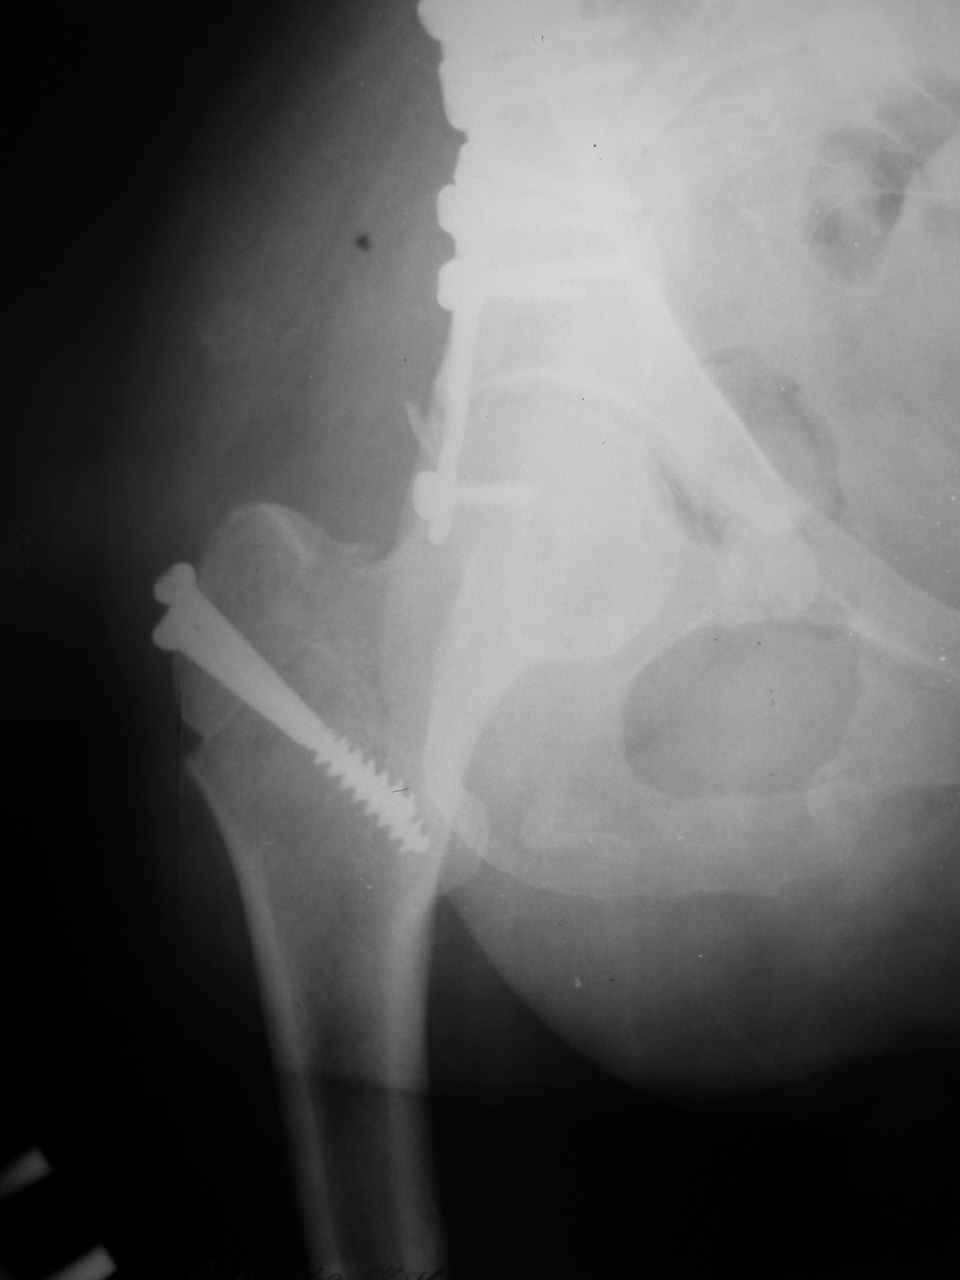

форуме и скелетном вытяжении. С репозицией и фиксацией задней колонны и отдельно задне-верхней стенки впадины проблем не возникло. Послеоп. Рг граммы в приложении. Если возникнут какие-либо дополнения или поправки - был бы признателен.

Причиной обращения к сообществу были возникшие непосредственно после операции сомнения и разочарования полученным качеством репозиции: а надо ли было трогать перелом вообще, репозиция передней колонны технически была очень сложна для меня, хотя реконструкции была в той же последовательности, что Д-р А.В.Рунков рекомендовал, в какой-то момент безуспешных манипуляций стал думать о *вторичной конгруэнтности*, которую не так давно обсуждали на

Илеофеморальный доступ не совсем передний и сравнительно с илеоингвинальным, и Кохера-Лангенбека открывает весь наружный таз кроме самых передних отделов лонных костей, фиксацию которых я не ставил в задачу. Обширность диссекции, большая длительность операции и более высокий риск гетерооссификации - отрицательные моменты в обмен на возможность легче ориентироваться.